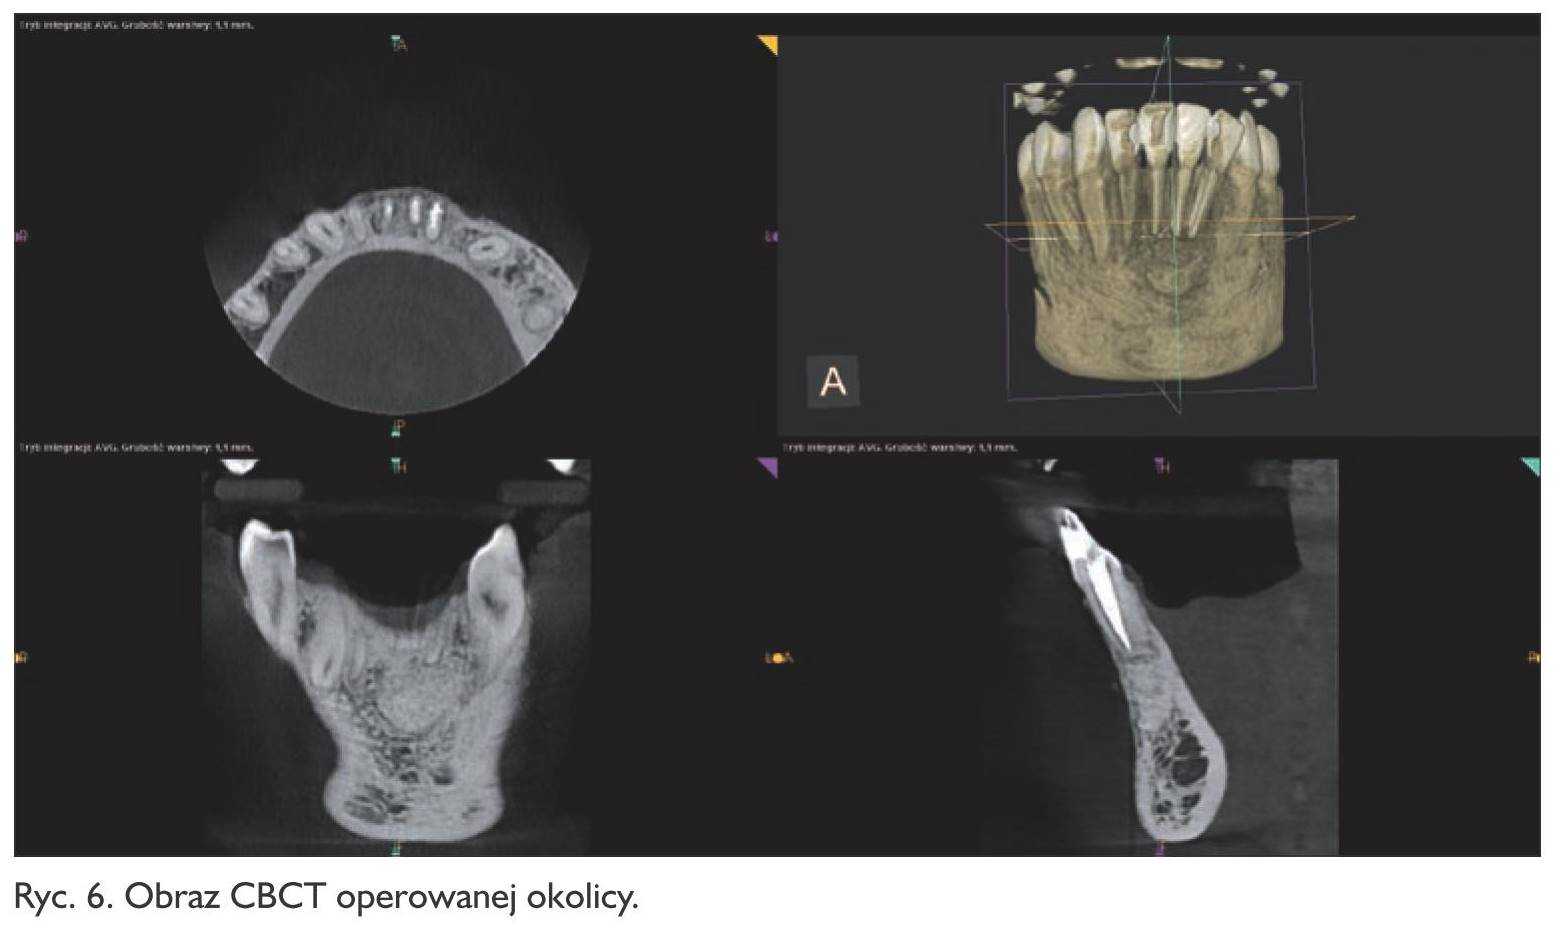

Pacjent zgłosił się po tygodniu w celu usunięcia szwów. Rana goiła się prawidłowo. W opisie badania histologicznego wysłanego materiału potwierdzono wstępną diagnozę cystis odontogenes. Kontrolne badanie tomograficzne wykonano po  6 miesiącach, wykazało ono pełną odbudowę kostną ubytku (ryc. 6, 7, 8, 9). Pacjent od czasu zabiegu nie odczuwał żadnych dolegliwości w tej okolicy.